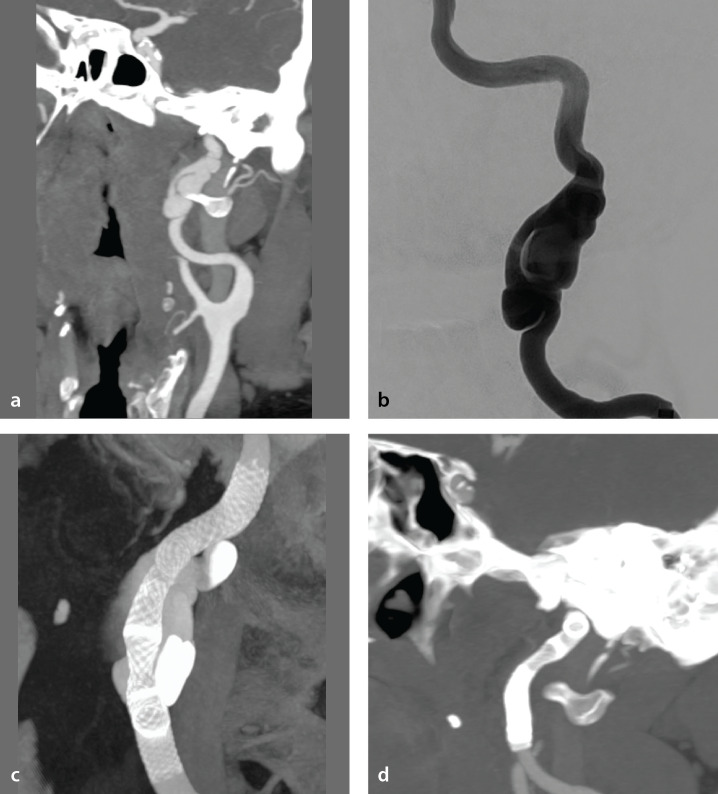

Abstract Image